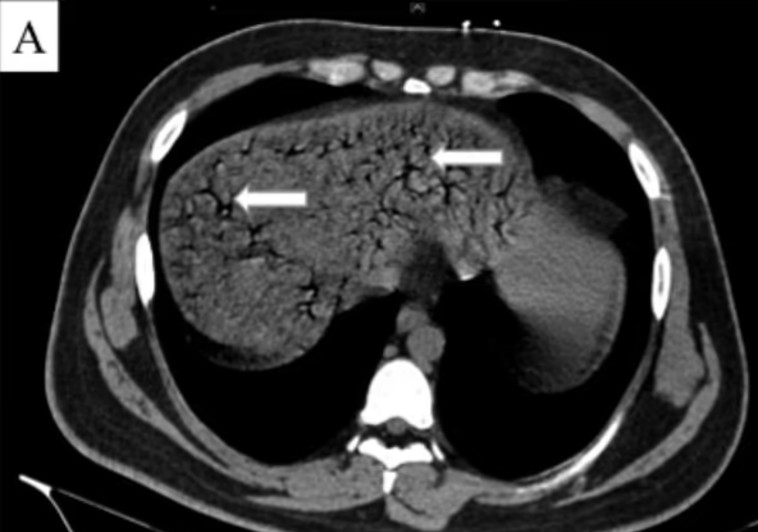

צילום ה-CT של המטופל

צילום ה-CT של המטופל | צילום: Chaoyang Hospital

כמו כן, בדיקת CT בכבד חשפה כי אותו הבחור סבל מאיסכמיה בכבד, שהיא מעין פגיעה הנגרמת כתוצאה מאספקת חמצן נמוכה לאיבר. המחבר הראשי של דו"ח המקרה, 'צאינג הו, הסביר כי הרופאים ניסו לנקז את הגז ממערכת העיכול של בן ה-22, אך בצער הוא לא הצליח לשרוד את הטיפול והלך לעולמו אחרי 18 שעות מתחילת ההליך הרפואי.